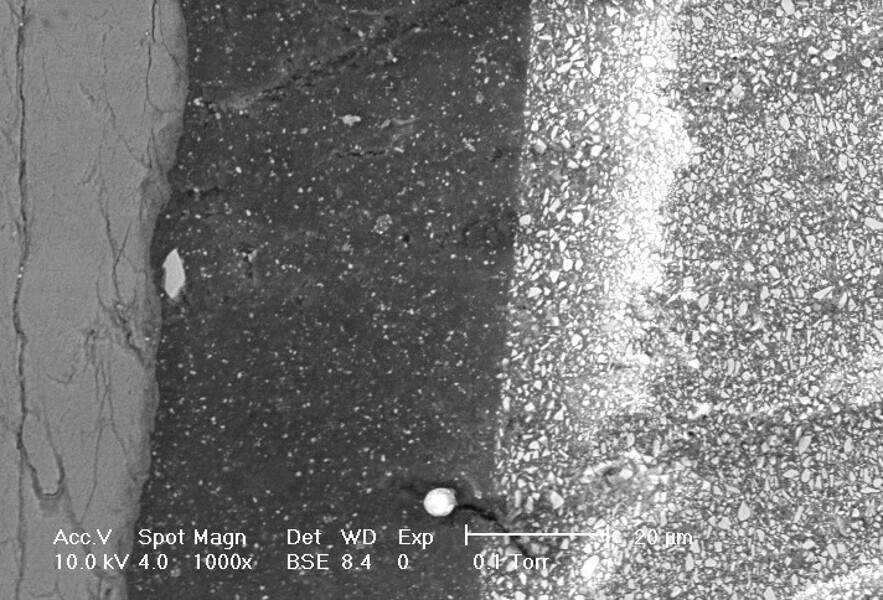

Fig. 12: Microscopic view of demineralised dentine and penetration of the hybrid layer into dentinal tubules.[5]